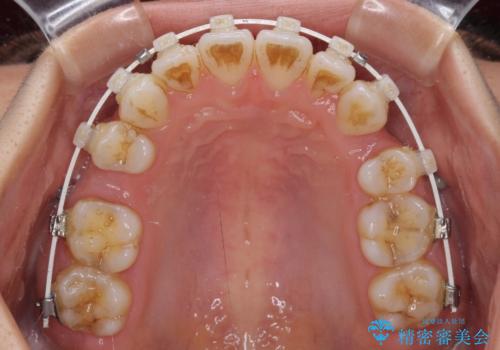

- 審美装置

- 八重歯と口元の突出感を気にして来院された患者様です。

歯列が前方に突出しており、上下の正中がズレていたため、左側は上下第一小臼歯を、右側は上下第二小臼歯を抜去し、ワイヤー装置による矯正治療を行うこととしました。

当初はインビザラインによる矯正治療をご希望でしたが、正中を合わせたいことや、口元の突出感を改善したいことから、ワイヤー矯正を強く推奨しました。

治療期間は2年に満たず、スッキリとした口元に仕上がりました。